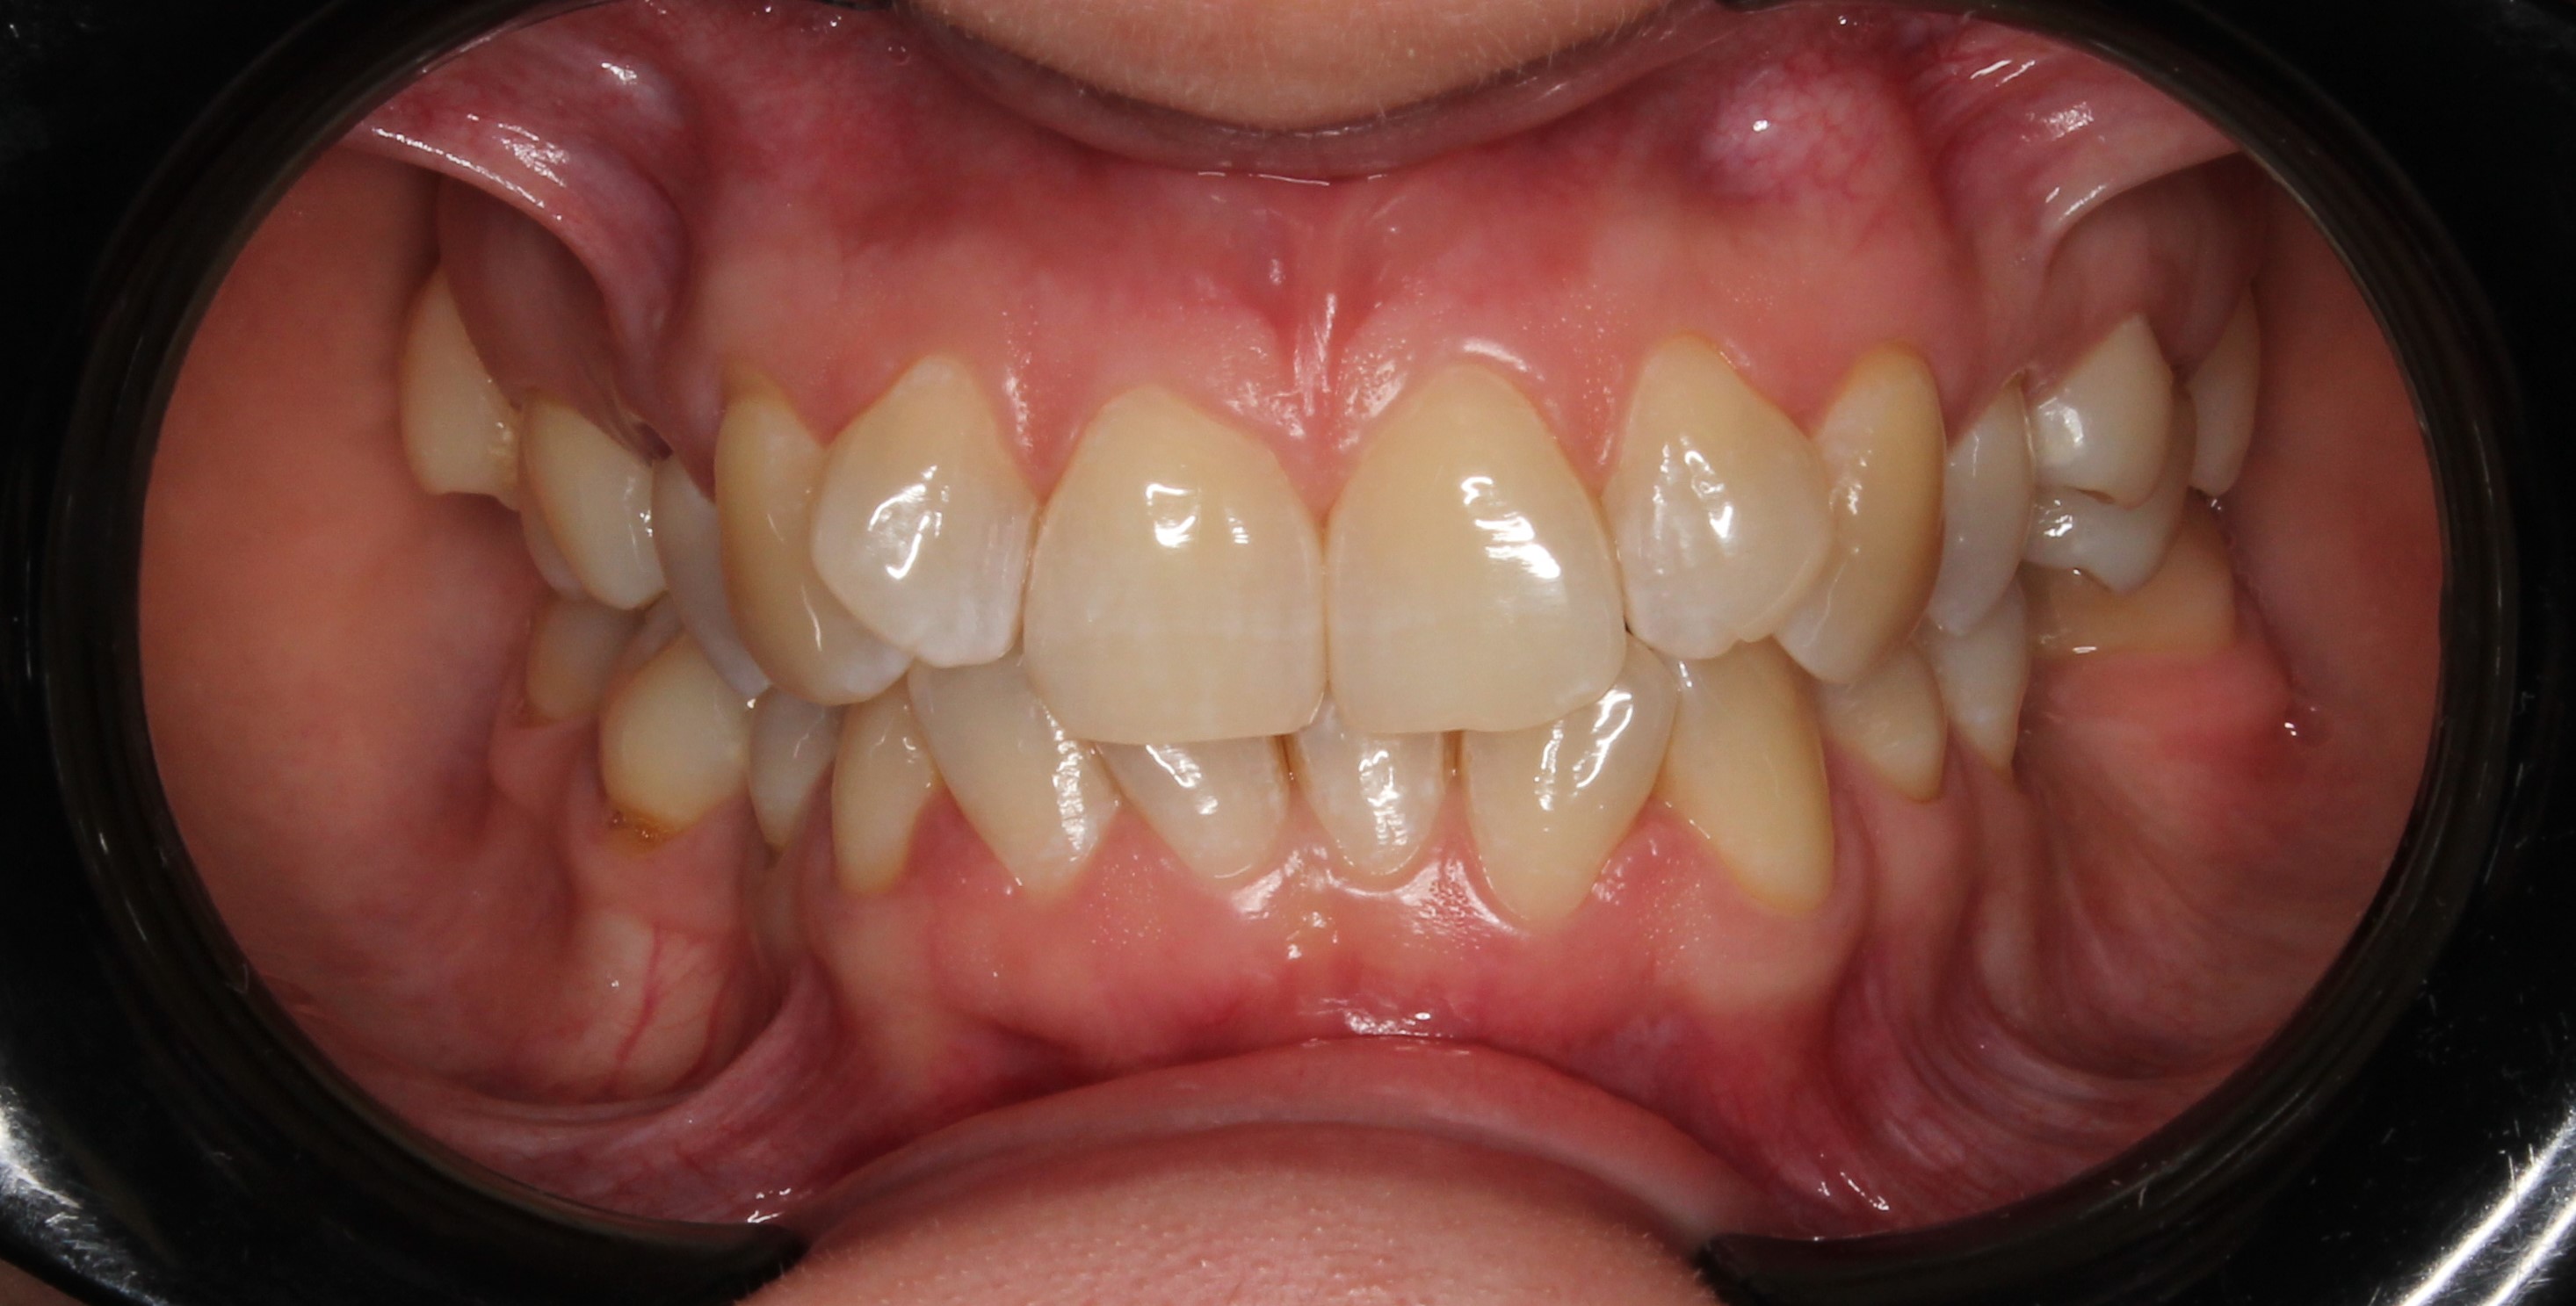

До и После: Фиксация элайнеров Eurokappa на зубы

Начало лечения на элайнерах Eurokappa. Фиксация аттачментов и установка незаметных капп для выравнивания зубов.